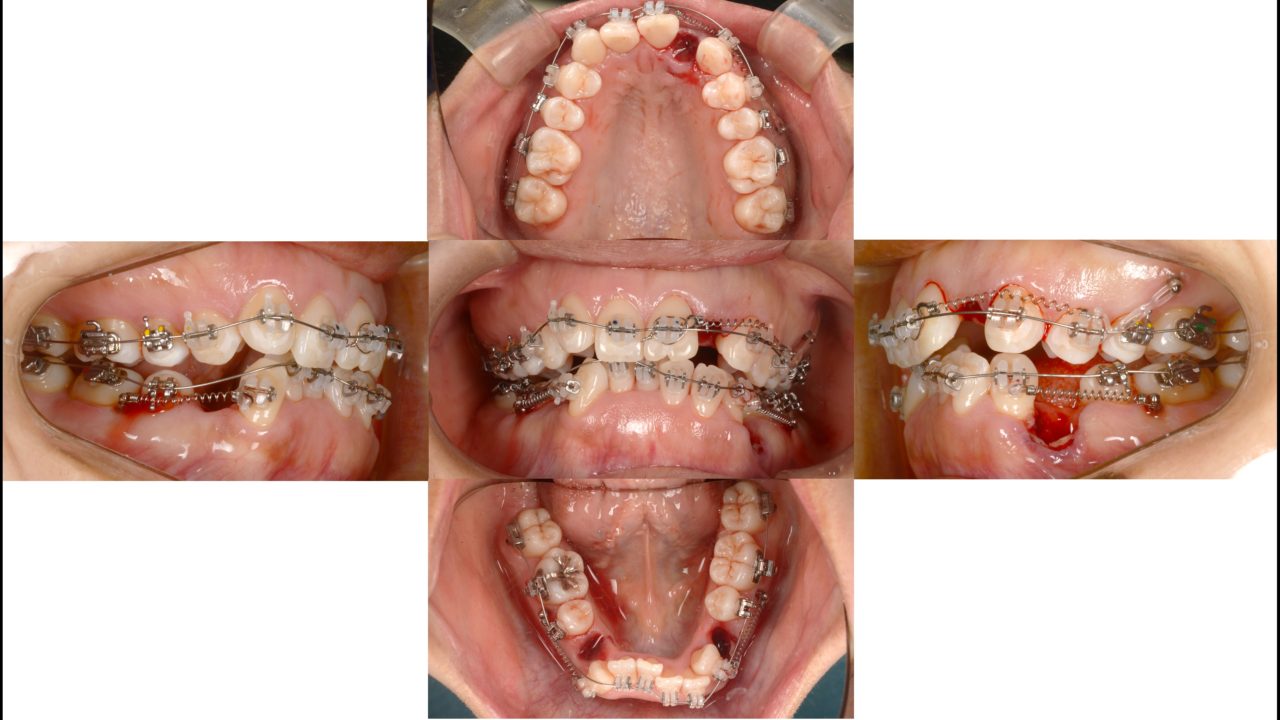

矯正治療開始 2018.6.15

矯正治療終了 2020.8.6

| 備考 | 前歯の凸凹が気になるとのことでした。旦那さんも当院で矯正治療を受けていたので、奥さんもついでに治すことになりました。左上側切歯は失活しており、変色が目立つ状態でした。また、左下第1小臼歯は歯頚部に大きなむし歯があり、歯肉退縮が著しい状態でした。叢生を解消するために抜歯が必要だったので、この状態の悪い2本と右下第1小臼歯の全部で3本を抜歯することにしました。治療後は口元の印象が劇的に良化しました。 |